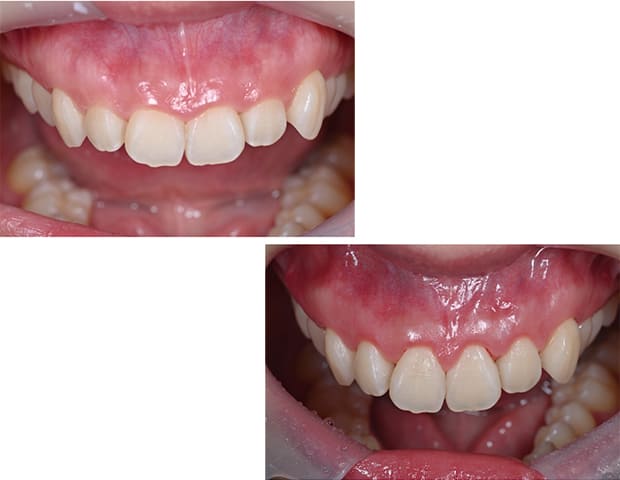

Case01

- 原因

- ガミースマイル

- 治療回数

- 1回

- 治療期間

- 術後治癒も含めて約1か月

- 治療内容

- ガミースマイル改善治療

- 治療費用

- 121,000円

(1ブロックあたり、6前歯部分)

笑った時に歯茎が見えてしまうガミースマイルを改善したいとのことでご来院された患者様です。術後も大変満足していただきました。